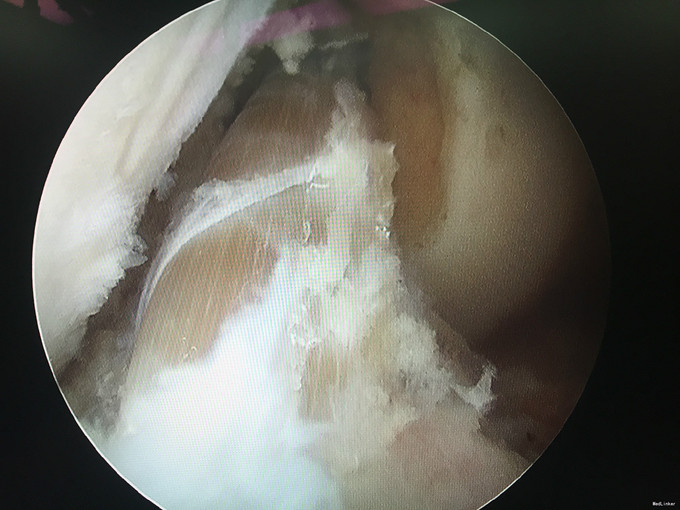

左膝扭伤后13年近1年反复不稳伴疼痛。 患者,男,39岁,13年前运动时扭伤左膝关节,当时未予重视,近1年出现左膝不稳伴疼痛,以上下楼、运动时明显,无法进行正常运动。遂于外院检查MRI(2015年3月)示:左膝关节退行性改变、左膝前交叉韧带信号异常、半月板信号异常、左膝关节内积液。为求进一步诊治来我门诊就诊,结合病史及体征,诊断“左膝半月板损伤、左膝前交叉韧带损伤”并收入院行进一步治疗。

入院诊断:左膝半月板损伤、左膝前交叉韧带损伤 治疗:入院后行左膝关节镜下外侧半月板成形+髁间窝成形+前交叉韧带自体肌腱重建手术。